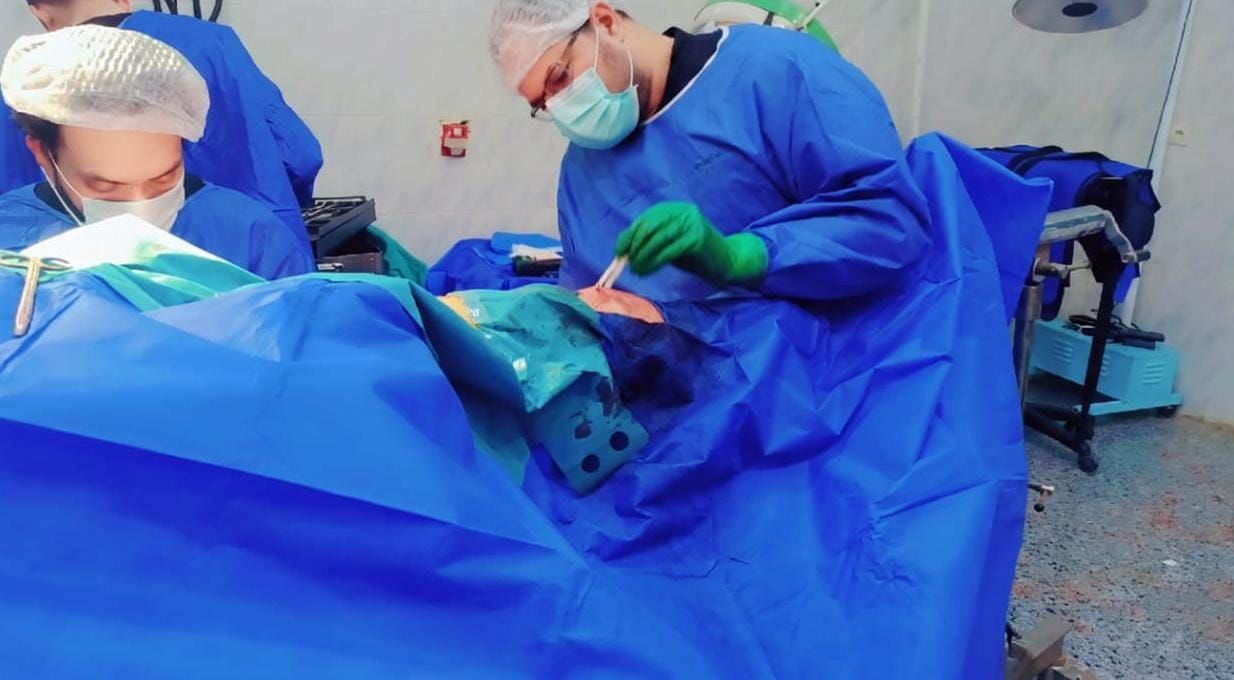

وفور وصول المصاب إلى قسم الطوارئ، جرى التعامل الفوري معه، وتم اتخاذ القرار الطبي العاجل بإجراء جراحة المسمار النخاعي التشابكي دون فتح موضع الكسر، بما يتوافق مع أحدث البروتوكولات الطبية العالمية. واستغرقت العملية نحو ساعتين ونصف فقط، غادر بعدها المريض غرفة العمليات في حالة مستقرة.

وأشادت إدارة المستشفى بالتنسيق الكامل والاستجابة السريعة لأفراد الفريق الطبي المشارك، والذي ضم أخصائيي العظام الدكتور أحمد جمال الدين، والدكتور عبد الرحمن كرم، وأخصائي التخدير الدكتور ميلر جبران، إلى جانب فريق التمريض المتميز: مها ناصر جمال، وسناء حشمت.